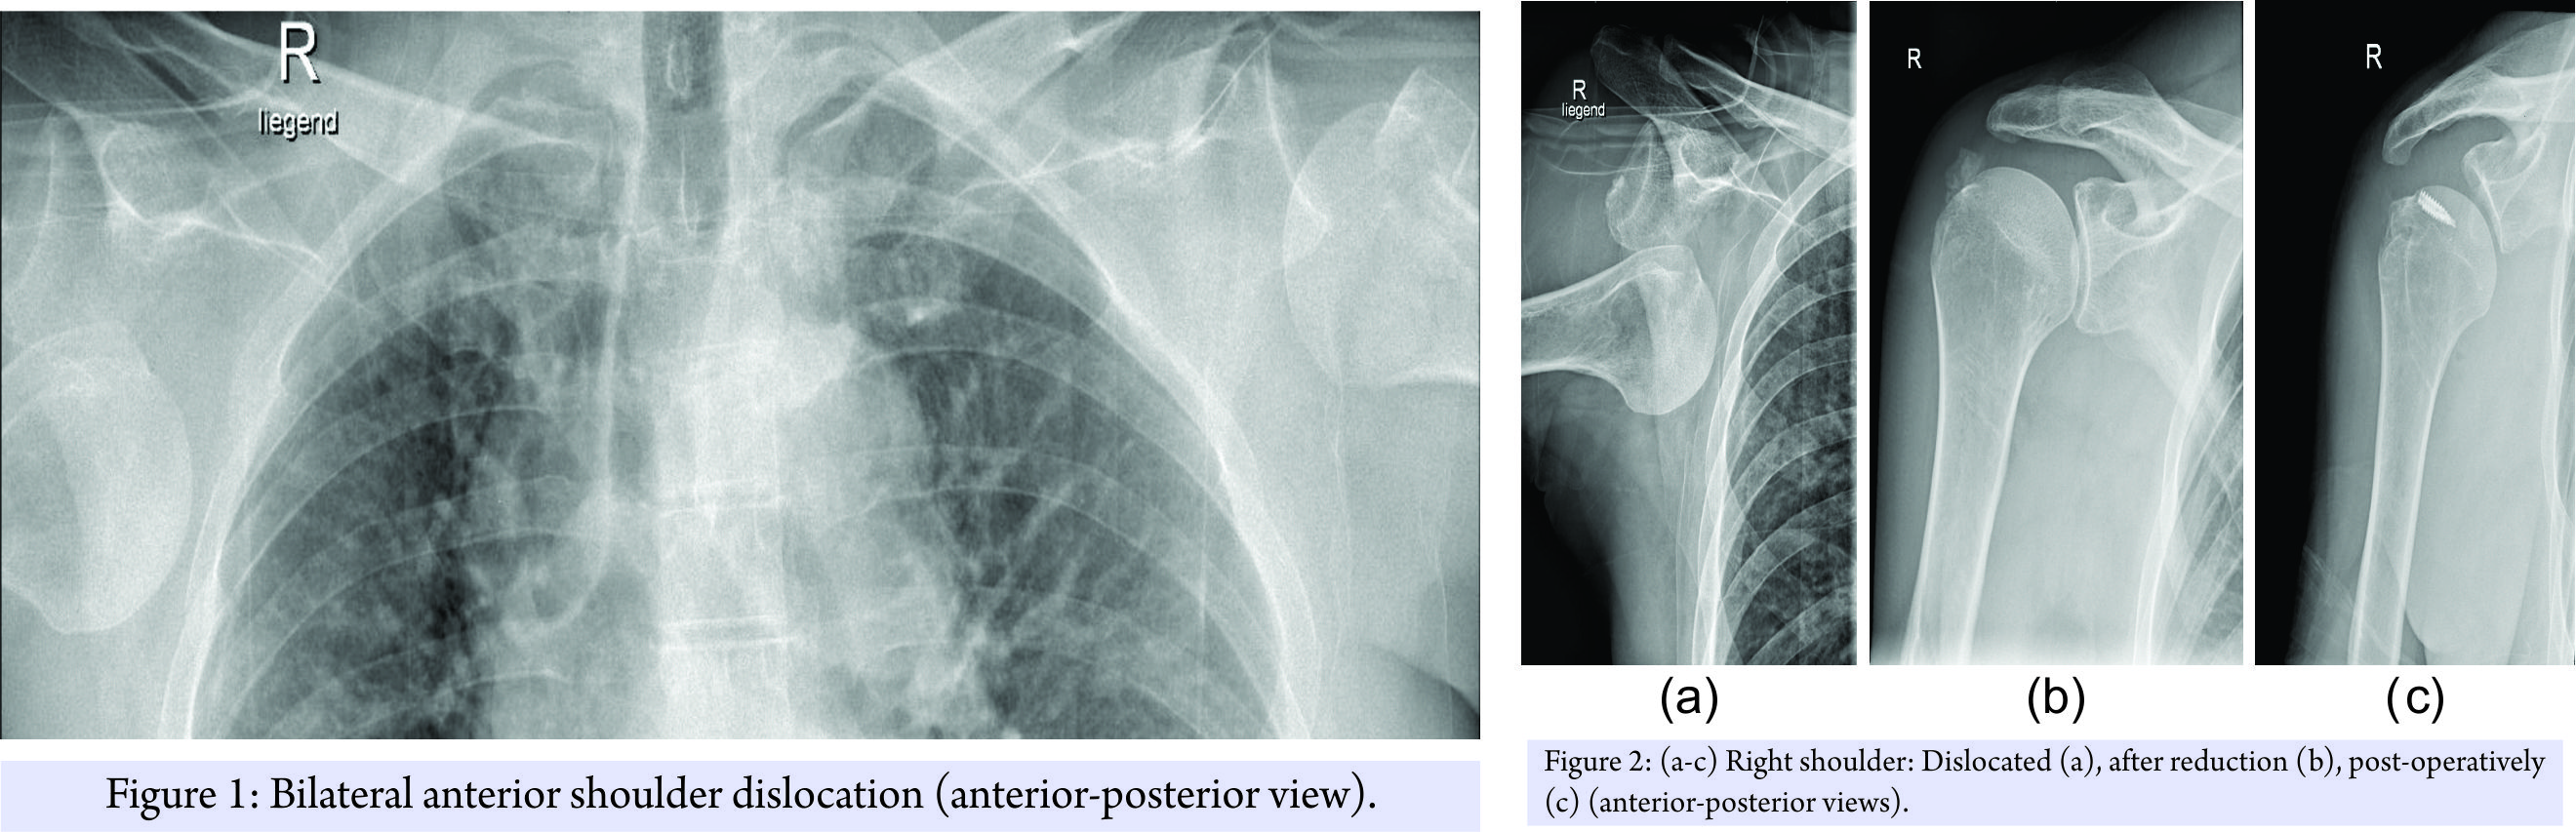

The patient was managed acutely on the slope and in our emergency room, according to ATLS principles, with a presenting GCS of 10 – E3V3M4. Full clinical examination was supplemented with imaging including a FAST scan and radiographs of shoulder joints, thorax, and pelvis. These confirmed the clinically suspected bilateral anterior shoulder dislocation combined with a four-part proximal humerus fracture on the left side and an osseous rotator cuff avulsion on the right side. The patient was neurovascular intact (Fig. 1, 2a and 3a).

In the emergency room, both dislocations were consecutively reduced under sedation using the traction-counteraction-technique (Fig. 2b and 3b). No neurovascular deficit was detected post reduction. The right shoulder was immobilized in a Gilchrist bandage and the left shoulder in a Desault’s bandage before performing a computed tomography (CT)-scan of the head to successfully eliminate possible cerebral hemorrhage or skull vault injuries.

As the patients recovering progressed, a magnetic resonance imaging (MRI) scan of the right shoulder was performed 3-day post-injury to clarify the soft-tissue damage and subsequently a single-row rotator cuff repair using two 5.5 mm TwinFix® anchors (Smith & Nephew; London, United Kingdom) was performed. An additional Pulley-lesion was treated with a biceps tenodesis with fixation of the tendon to the intertubercular sulcus using a 5.5 mm Footprint® anchor (Smith & Nephew; London, United Kingdom). The Hill–Sachs lesion was insignificant and did not require any further treatment (Fig. 2c). Post-operatively, the left shoulder was immobilized in a Velpeau-sling for 4 weeks and the right shoulder in an abduction splint for 6 weeks. Passive mobilization of both shoulders was started immediately on the first post-operative day, followed by increasing active and assistive mobilization. On the right shoulder, progressive adduction and a steady build-up of strength were initiated after 6 weeks. On the left shoulder, full mobilization was allowed following clinical and radiological confirmation of fracture consolidation. Physiotherapy (3 times a week), aquatic therapy (2 times a week), and a 3-week stay in a rehabilitation facility 2-month post-injury completed the post-operative care. The patient was discharged in good general condition with a total inpatient stay of 11 days. The 30-day follow-up assessment showed a still restricted range of movement while the 6-month follow-up assessment demonstrated bilateral considerably improved range of movement (Table 1). At the 2-year follow-up assessment still no evidence of implant failure, recurrence of dislocation or instability was observed.